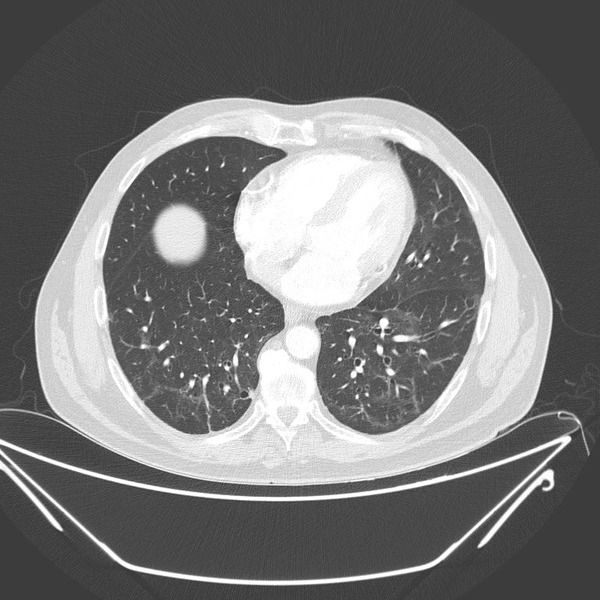

Prof. Dr. Güner Sönmez, "Evre 4 akciğer kanseri hastanın Covid 19 öncesi ve sonra çekilen akciğer tomografisi.

Akciğerdeki metastaz kaybolmuş. Daha önce de bir lenfoma hastasını paylaşmıştım; Covid sonrası tamamen lenfoma bulguları kaybolmuştu.

Muhtemelen Corona virüse karşı oluşan antikorlar ve hücresel bağışıklık, kanser hücrelerine de müdahale ediyor." ifadelerini kullandı.